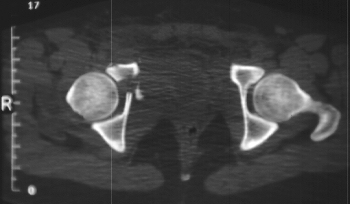

Radiographs:

Radiographs revealed a vertical buckle fracture of the right inferior sacrum, oblique fractures of the superior and inferior rami on the right and a fracture through the medial acetabulum. Obturator and iliac oblique inlet and outlet pelvic views, and a thin cut CT with 3-D reconstruction of the acetabulum were performed. These elucidated a comminuted anterior wall with fracture line extending to the posterior column. The posterior column was non-displaced. The pelvic fracture was non-displaced.

Assessment:

1. Right T-shaped acetabular fracture with anterior wall comminution.